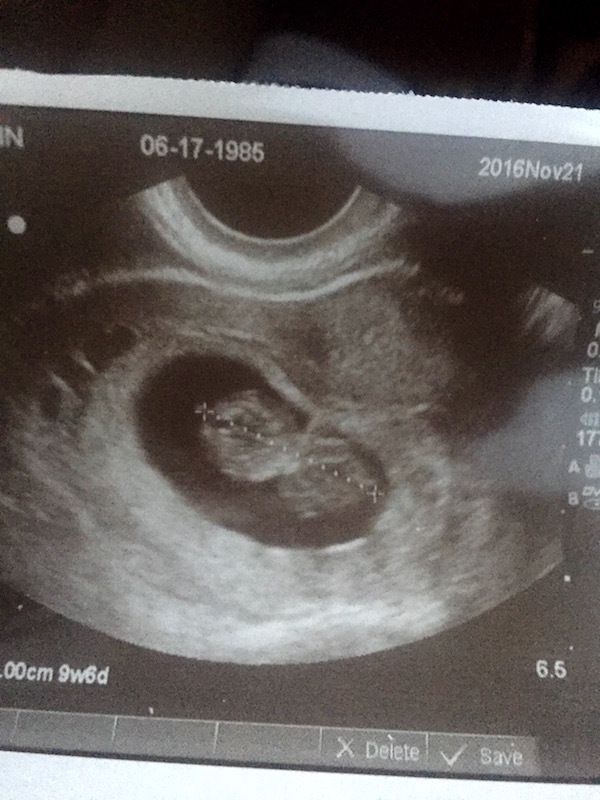

How far along were you when you found out, and how far along are you now?

I believe I was around 3 weeks when I first found out. The problem was I don't have regular periods, so it is tough to say for sure, but it was confirmed after having an ultrasound confirming how many weeks I am. I am currently just a few days shy of 12 weeks.